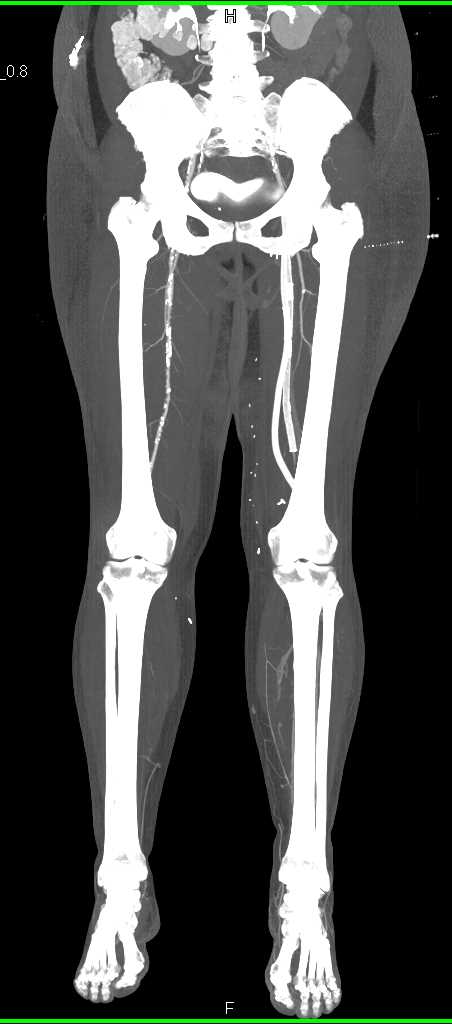

Artifact from Bilateral Total Knee Replacement (TKR)